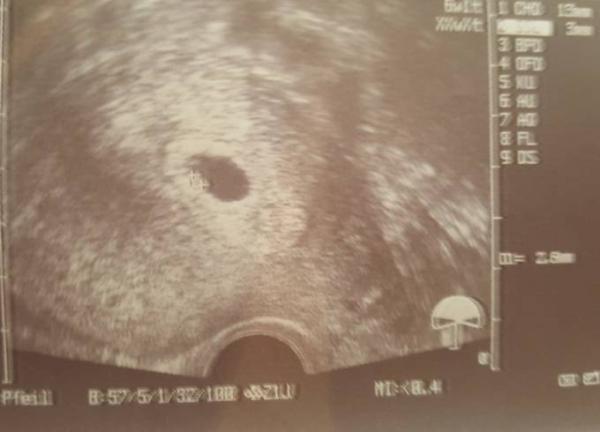

Geschafft Herzlein blubbert. Ist alles zeitgerecht entwickelt. Bild ist leider nicht so deutlich da sie das Babylein dort vermessen hat.

Heike ich drücke dir dolle die Daumen. Wie weit bist du? Tante 3 mm ist das Babylein. Sagt mal wie macht ihr es oder habt es gemacht den AG zu informieren? Nu noch bis 15 Ihr warten das ich hcg prog und e 2 werte bekomme.